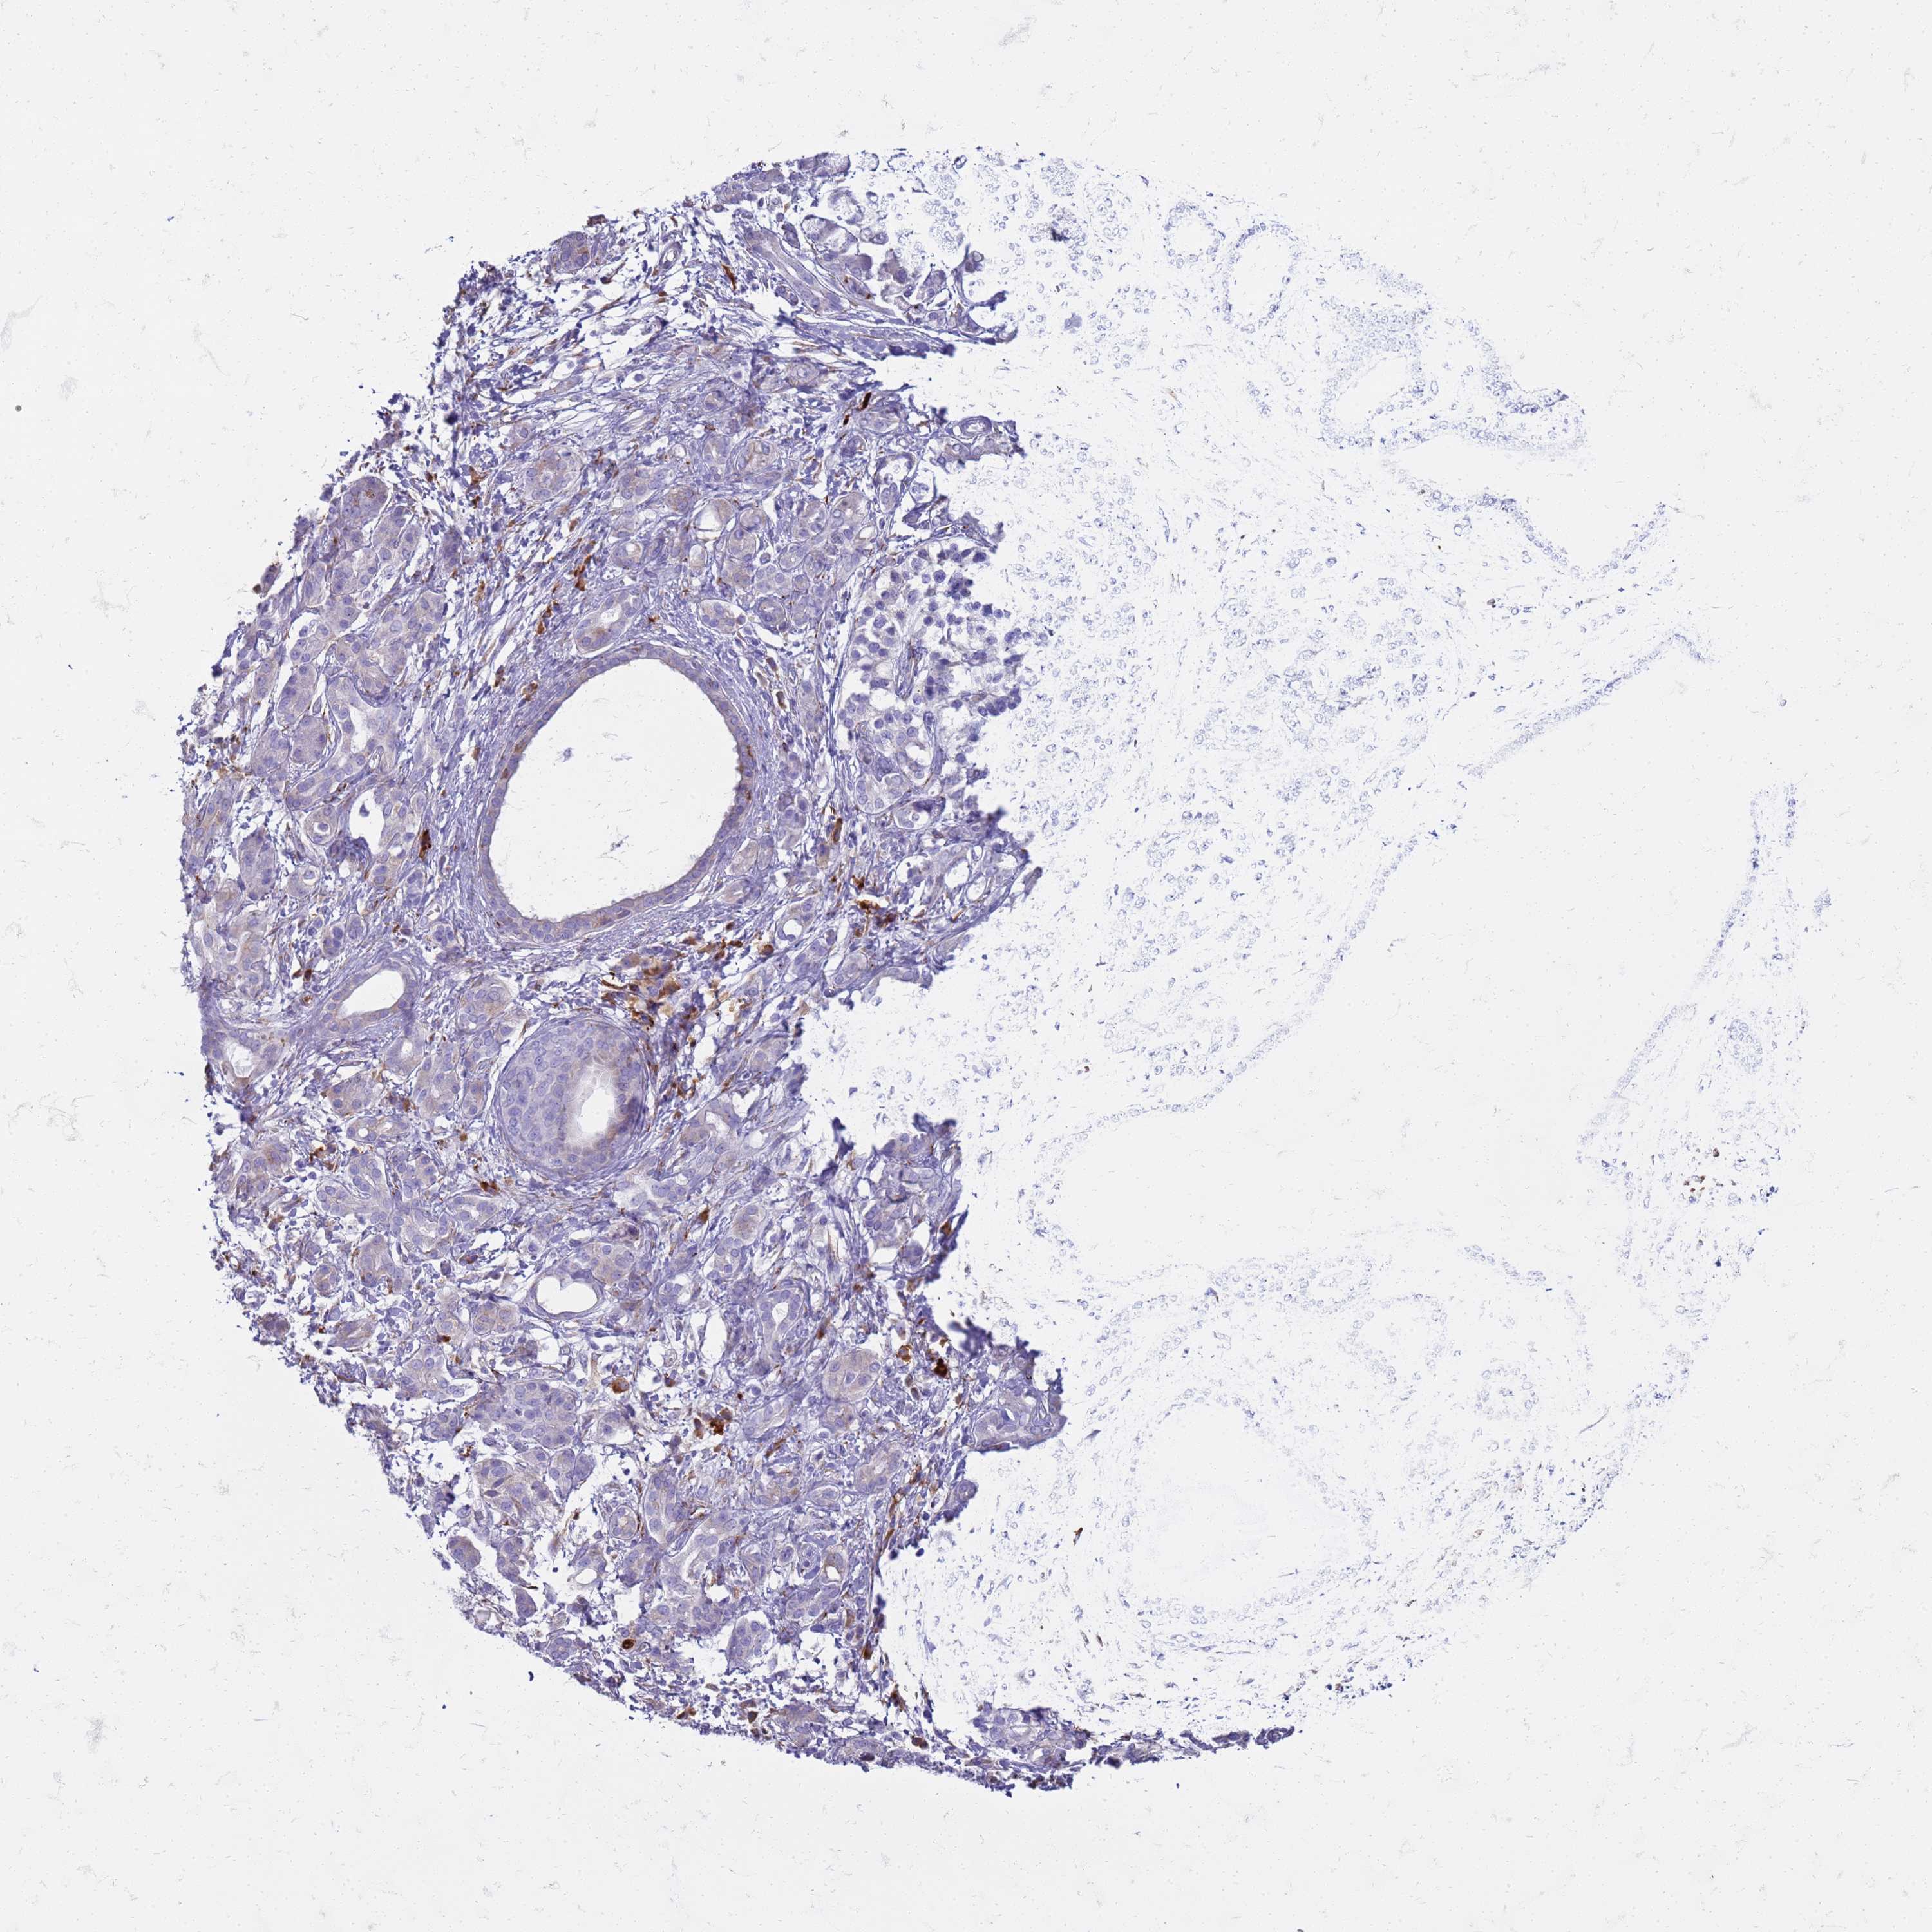

PANCREATIC CANCER - Protein expressioni

A mouse-over function shows sample information and annotation data. Click on an image to view it in a full screen mode. Samples can be filtered based on level of antibody staining by selecting one or several of the following categories: high, medium, low and not detected. The assay and annotation is described here.

Note that samples used for immunohistochemistry by the Human Protein Atlas do not correspond to samples in the TCGA dataset.

Antibody stainingi

Antibody staining in the annotated cell types in the current human tissue is reported as not detected, low, medium, or high, based on conventional immunohistochemistry profiling in selected tissues. This score is based on the combination of the staining intensity and fraction of stained cells.

Each image is clickable and will lead to virtual microscopy that enables deeper exploration of all samples and also displays staining intensity scores, fraction scores and subcellular localization as well as patient and tissue information for each sample.

Antibody HPA046583

Staining

High

Medium

Low

Not detected

Intensity

Strong

Moderate

Weak

Negative

Quantity

>75%

75%-25%

<25%

None

Location

Nuclear

Cytoplasmic/membranous

Cytoplasmic/membranous,nuclear

Adenocarcinoma, NOS

Adenocarcinoma, metastatic, NOS